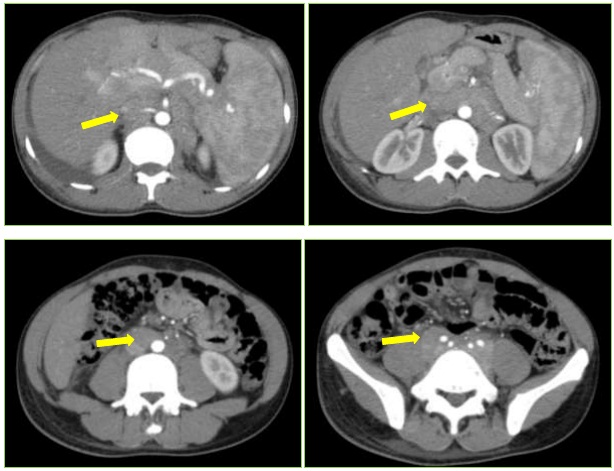

Hình ảnh Cắt lớp vi tính ổ bụng trước điều trị:

Hình 2: Nhiều hạch ôm quanh động mạch chủ bụng, động mạch chậu 2 bên và tiểu khung 2 bên (mũi tên vàng)- theo dõi lymphoma